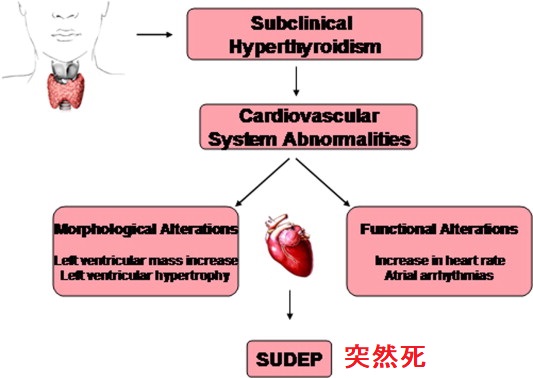

治療せずに放置すると体に影響が出る

潜在性甲状腺機能亢進症を治療せずに放置すると、身体にいくつかの悪影響を及ぼす可能性があります。